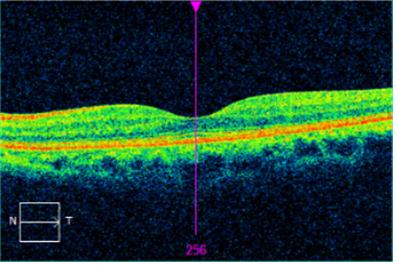

• 건강한

• 비삼출성 황반변성